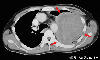

| 年齢 | 50-54 |  |    ■症例詳細データ | 病理学分類 | 転移性腫瘍/ |  | 症例の種類 | 典型例 |  | 性別 | 男性 |  | 年齢 | 50-54 |  | 主訴 | 咳、血痰。 |  | 病歴 | 咳、血痰があり近医を受診し、左上肺の塊状影、高度貧血を指摘され、紹介にて外来受診した。 |  | 既往歴 | 特記すべきことなし。 |  | 現症 | 全身状態良好。眼瞼結膜は貧血様、表在リンパ節等触知せず。 |  | 一般検査データ | 血液一般---WBC:23010/mm3,  RBC:235X104/mm,   Hb:5.0g/dl,  Plt:44.1104/mm3 生化学---Tp:5.2g/dl,  Alb:3.0g/dl,  T.Bil:0.4mg/dl,  GOT:18IU/l,  GPT:15IU/l,  CRP:2.69mg/dl

|  | 経過 | 胃と大腸の画像検査では著変を認めなかったため、小腸X線造影検査が行われ、空腸の腫瘍性病変が発見され、小腸の部分切除術が施行された。組織学的には未分化癌で、他臓器からの転移が疑われた。その後各種の診療にもかかわらず肺病変は増大。また、腹部にも病変が出現し、再び切除を余儀なくされた。 |